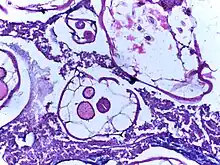

![]() | |

| Ascaris worms (one type of helminth) in the small bowel of an infected person (X-ray image with barium as contrast medium) | |